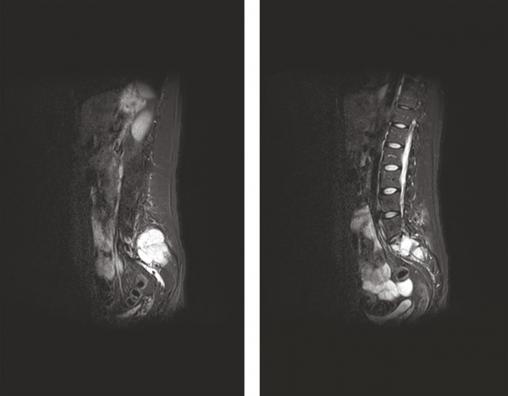

L’IRM couplée du rachis et du bassin a révélé la présence de trois lésions tissulaires vertébrales (en T3, T4 et T5) et d’une lésion plus volumineuse de l’aileron sacré gauche infiltrant le premier trou sacré gauche (fig. 3). L’hypothèse de lésions métastatiques a alors été privilégiée.